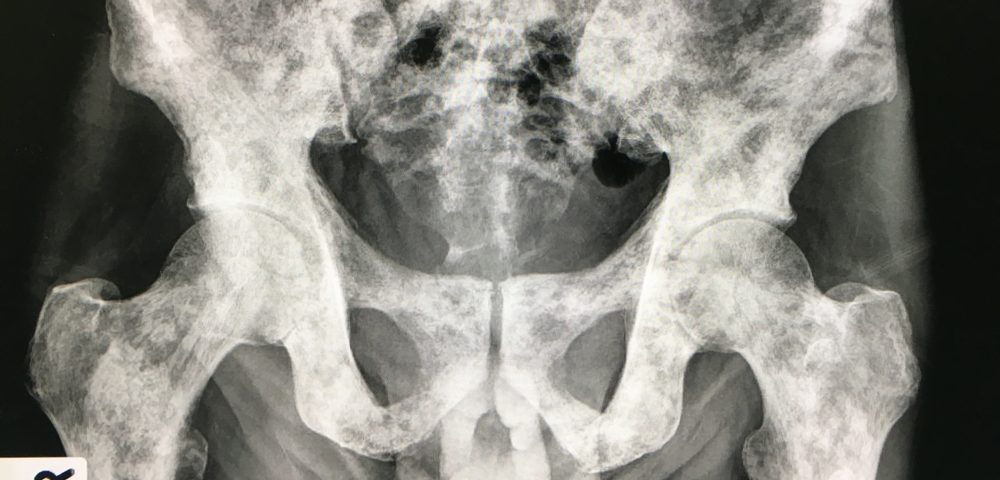

- Далее по частоте следуют метастазы в костях таза — почти половина всех случаев. Типичные локализации — метастазы в подвздошной кости и лонных костях.

Примерно у 80% больных костные метастазы локализуются в позвоночнике, костях таза, ребрах, грудине и черепе [5—7]. American Joint Committee on Cancer за 2009 г. приводит данные частоты метастатического поражения костей с учетом локализации (табл.

2).